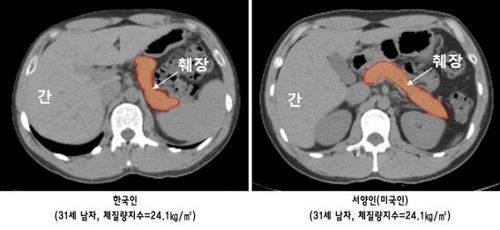

임수 분당서울대병원 내분비내과 교수팀은 컴퓨터단층촬영(CT)을 통해 체격이 유사한 30대 한국인과 서양인을 43명씩 이들의 췌장 용적 등을 비교 분석해 이런 사실을 확인했다고 밝혔다.

연구팀에 따르면 한국인은 서양인보다 췌장의 크기가 12.3% 정도 작은 반면 췌장에 침착된 지방의 양은 22.8% 많았다.

췌장의 인슐린 분비 능력은 한국인이 서양인보다 36.5% 떨어지는 것으로 나타났다.

서양인과 체형이 비슷하더라도 한국인의 췌장 크기가 절대적으로 작고, 인슐린 분비 능력마저 떨어진다는 것이다.